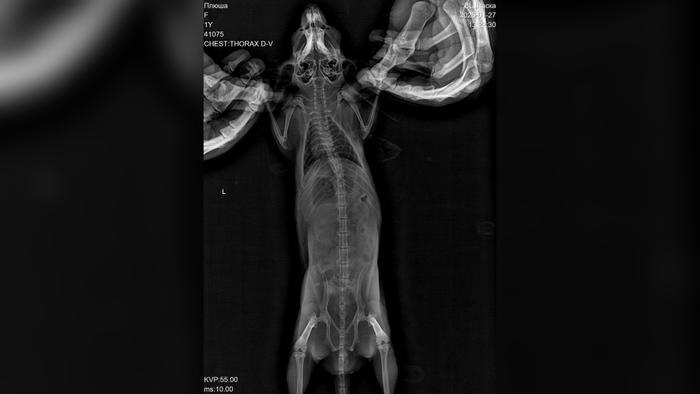

Пока хозяина не было дома грызун каким-то образом выбрался из своей клетки днём. Вечером Билан нашёл Плюшу возле музыкального оборудования, у неё была заметная рана на носу. Исполнитель немедленно связался с ветеринаром и получил инструкции по оказанию первой помощи, однако к утру состояние шиншиллы резко ухудшилось. Из-за сильного снегопада и пробок путь до клиники, находившейся в 60 километрах, занял почти два часа.

«За неё боролись около четырёх часов, но к сожалению, травмы оказались несовместимыми с жизнью. Диагноз — черепно-мозговая травма и отёк головного мозга», — написал он.

По словам Билана, он сначала предположил, что шиншилла могла получить травмы из-за кота Шахтёр, поскольку он хищник. Однако, по всей видимости, Плюша самостоятельно выбралась из клетки и с разбега врезалась в панорамное окно, что принесло тяжёлые травмы. Артист обратил внимание на то, как важно заранее понимать, с какими трудностями можно столкнуться, когда заводишь подобное животное.